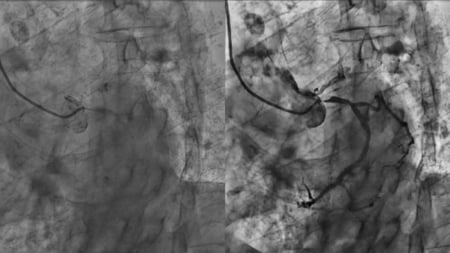

PCI for complex bifurcation disease - LIVE Case

A 60-year-old male patient presented with an inferior STEMI one month ago, which was treated with RCA and LCx PCI. He was referred for LAD/diagonal PCI. The LV function was reduced (EF 45 %). The team performed a DK crush PCI, guided by IVUS.